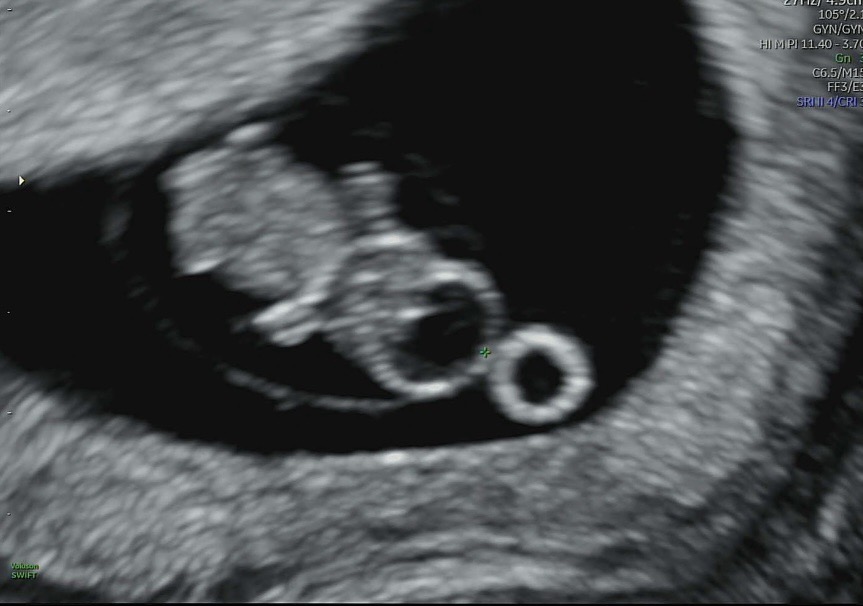

8주 1일차 하리보

하리보 보고왔어요 너무 귀여워서 살포시 올려보아요.. 🧸💛